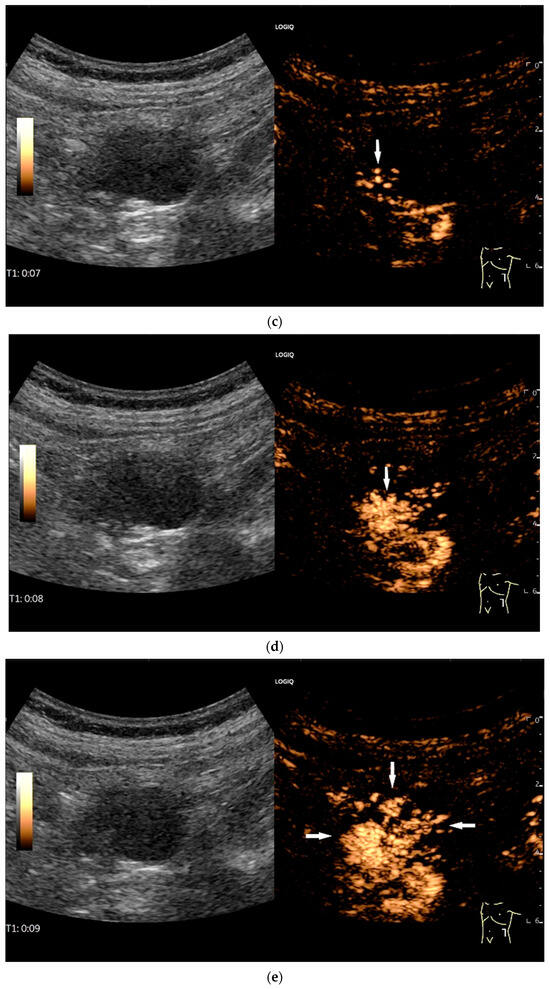

Figure 9.

Burkitt-Lymphoma. In a patient with weight loss, increased abdominal circumference, anemia, and physical weakness, the initial sonographic examination reveals an extensive tumor with intense hypoechogenicity and a connection to the jejunum in the left mid-abdomen. Despite its pronounced hypoechogenicity, a feeding vessel on CDI indicates a solid character (a). The tumor significantly thickens the wall and is intensely hypoechoic. The arrows point to the multisegmental hypoechoic wall thickenings (b). Normal wall structures are still visible (W), and the tumor extends beyond the wall (arrow) (c). In addition to delicate Kerckring folds (KF), there are significantly polypoid thickened KF with pronounced hypoechogenicity (d). The thickening of KF is very extensive (e). Wall thickening was found also in the stomach and colon and allowed endoscopic biopsy to establish the diagnosis.